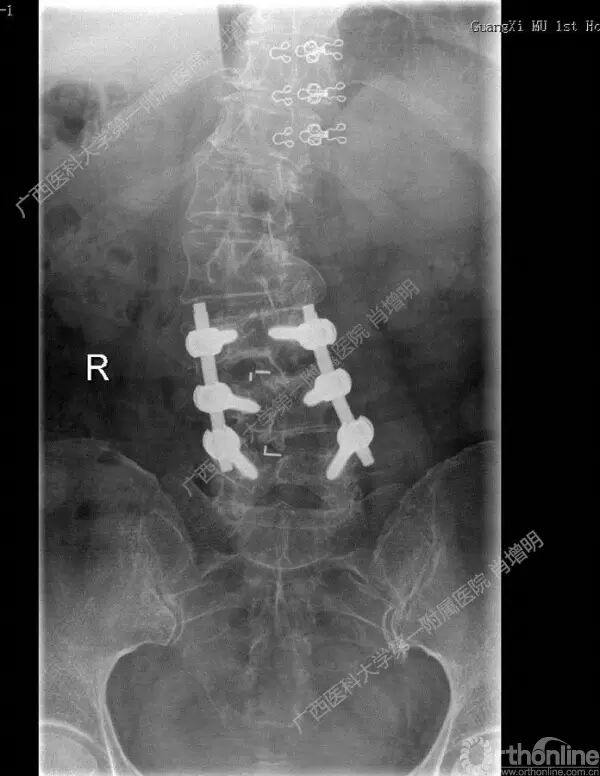

退变性脊柱侧凸是由于椎间盘退变后继发小关节退变,椎管和神经根管容积变化以及脊柱失稳,畸形等病理改变,以疼痛和神经压迫症状为主要表现的常见疾病。

退变性脊柱侧凸多发于50岁以上的中老年群体,是现代常见的老年疾病。多年来,针对该病的临床研究一直没有停步,广西医科大学第一附属医院肖增明教授细致地介绍了该病的诊疗进展。